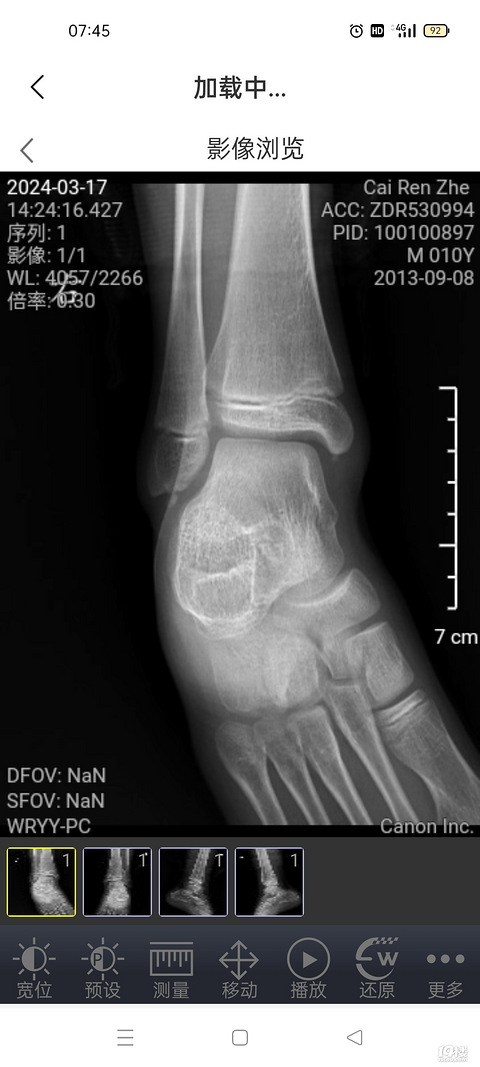

男娃身材一直偏矮,目前11岁5个月,身高143cm,骨领12.6了,偏大一岁多;体重86斤,拍了b超,身体已经快速在发育了,医生说按照这个快速发育的节奏,身高也应该快速增高,但并没有明显增高现象,预测身高160左右,男娃。医生给出了可以药物干预,也就是打生长针吧,有没有什么副作用?